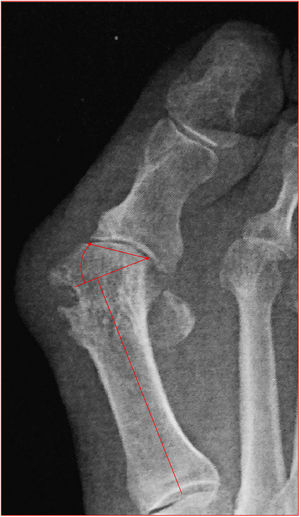

Angulo de desplazamiento articular proximal (PASA por sus siglas en inglés): mide el desplazamiento de la superficie articular de la cabeza del primer metatarsiano, un desplazamiento mayor a 10 grados es anormal e implica una deformidad angular del metatarsiano por si mismo. Se mide entre la perpendicular al eje del metatarsiano y una línea que corresponde a la superficie articular de la cabeza del primer metatarsiano. Cuando este ángulo es anormal no se puede reposicionar la falange con procedimiento de tejidos blandos aislado y requiere una osteotomía de realineamiento para desplazarla medialmente (fig. 6).